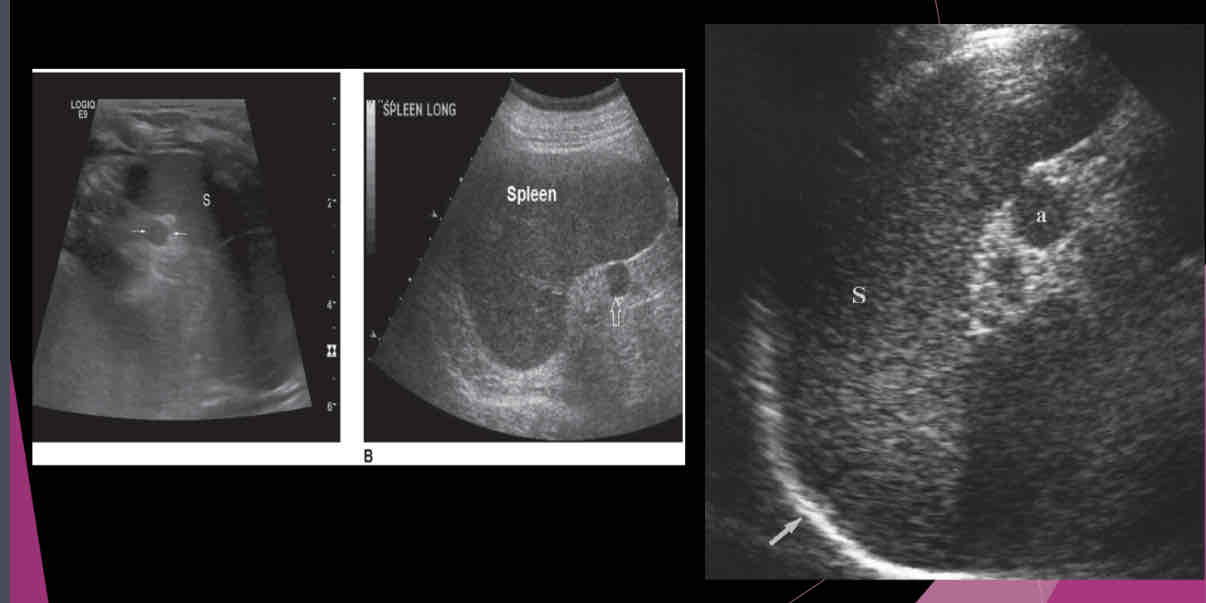

Describe the spleen on US?

-Homogeneous texture

- Echogenicity the same as or slightly below the normal liver echogenicity

- Smooth border at diaphragm

- Intercostal coronal view used to obtain spleen length

- Average length 11-13cm; usually decreases in size with age

- Usually 2/3 size of the liver

- Deep inspiration usually necessary to evaluate the entire organ

What is a relatively common anatomic variant?

accessory spleen (Splenule)

Most accessory spleens are small and measure between…

1.5 and 2.0 cm

An accessory spleen or splenule is _______ to spleen

hypoechoic

Isoechoic

hyperechoic

heterogeneous

Isoechoic